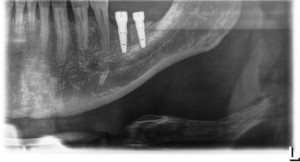

Authors: Andrea Fama , Davide Cavagnetto, Andrea Abate, Andrea De Filippis, Eleonora Mainardi, Luca Esposito

The term dilacerated refers to a dental element that has an alteration of the axial inclination of the crown with respect to the root. Dilaceration can occur at the crown-root junction with...